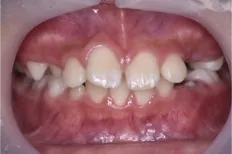

プレオルソの症例

Before

After

症例の概要

この患者さんは10歳の男の子で、前歯が出ている事を主訴に来院されました。

日中の1時間と就寝時に装着していただいて、舌の位置や飲み込みの指導を約6ヶ月使用した初診時と術後です。

比較をすると主訴の右上の前歯が内側に入ってきて、噛み合わせが深かった(噛んだ時に下の前歯があまり見えていない状態)のが浅くなり、

上の歯並びのアーチが狭かったのが、広がって綺麗に歯が並んできていることがわかります。

この様に状態によってはワイヤーを装着せずに、改善させることができます。